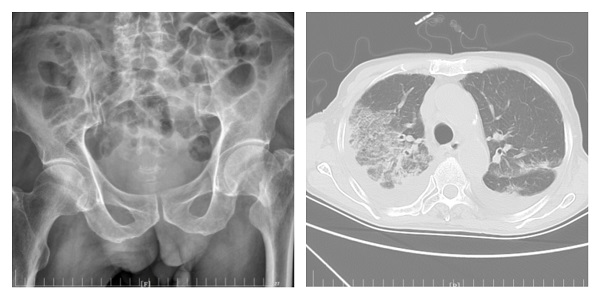

高龄老年人多存在骨质疏松,不慎跌倒骨折后影响行走,长期卧床极易并发肺部感染,如再新冠病毒感染,给治疗带来了巨大挑战。12月初以来,二一五医院骨五科陆续收治了多名骨折合并新冠高龄患者,经全院多科室通力合作...